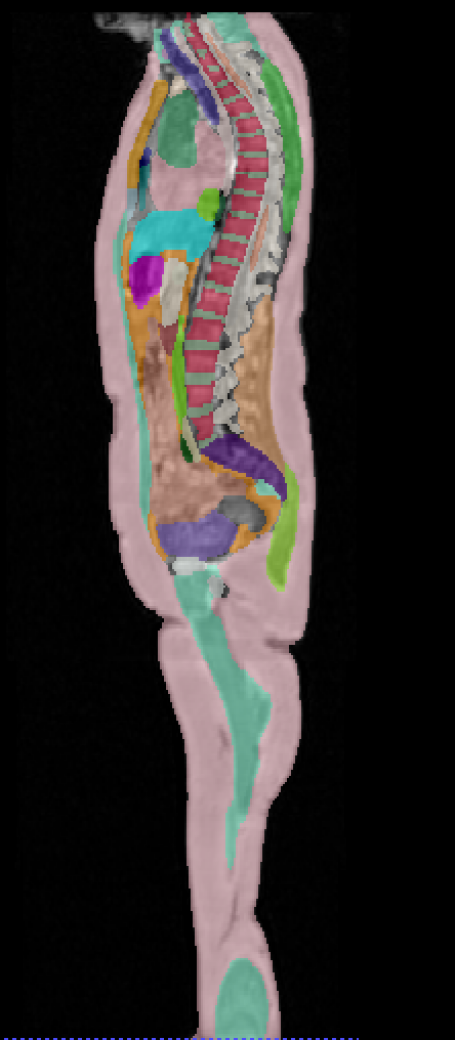

\captionof

figureUKBOB Size and Diversity. Our proposed UK Biobank Organs and Bones (UKBOB) is the largest labeled medical imaging dataset for segmentation, comprising body organs of 51,761 MRI 3D samples (17.9 M 2D images) and a total of more than 1.37 billion 2D masks of 72 organs. Left: we show label examples from UKBOB from axial, coronal, and sagittal views. Right: We show a plot of the size (number of 2D images) and diversity (number of classes) of our UKBOB compared to other medical images datasets. The size of the bubbles indicates 2D image resolution. This new scale in dataset size and diversity should unlock a new wave of applications and methods in the computer vision and medical imaging communities.